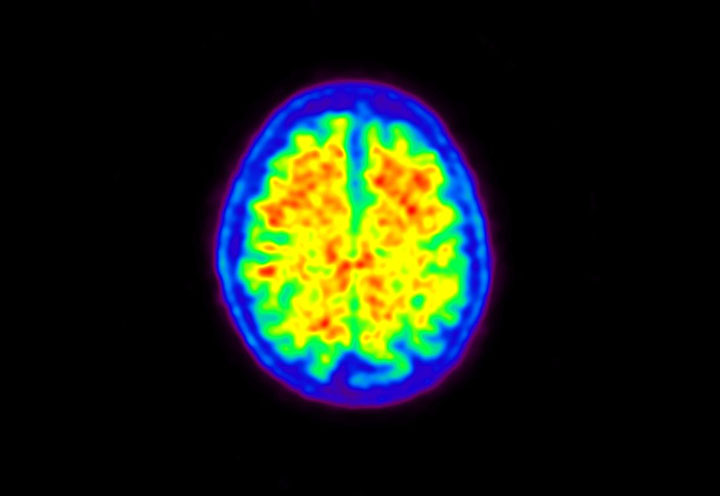

Head / Case5 : Amyloid

Axial

Courtesy : Kindai University Hospital

- Imaging protocol

- Injected dose: 4.27 MBq/kg, 18F-Flutemetamol

- Uptake time: 99 minutes

- Scan time: 20 minutes